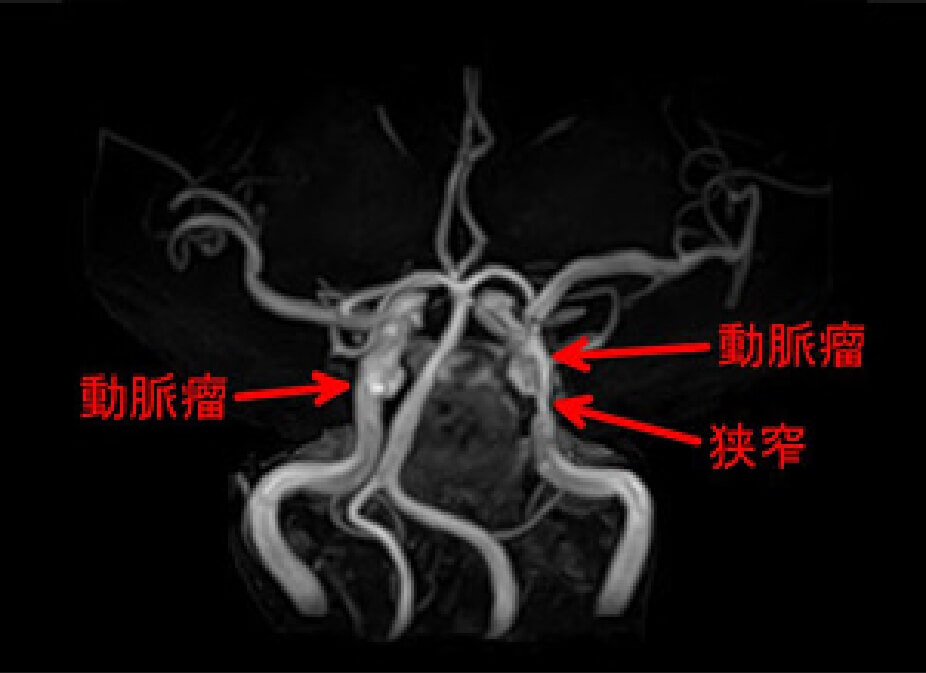

動脈瘤と狭窄の症例